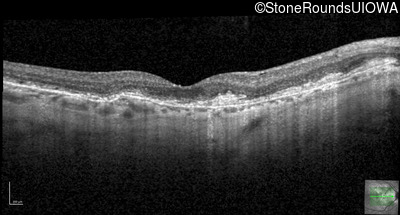

Optical Coherence Tomography - Right - 20/25 +1

Exemplar / OCT Stack

OCT Stack

Optical Coherence Tomography - Left - 20/25 +3